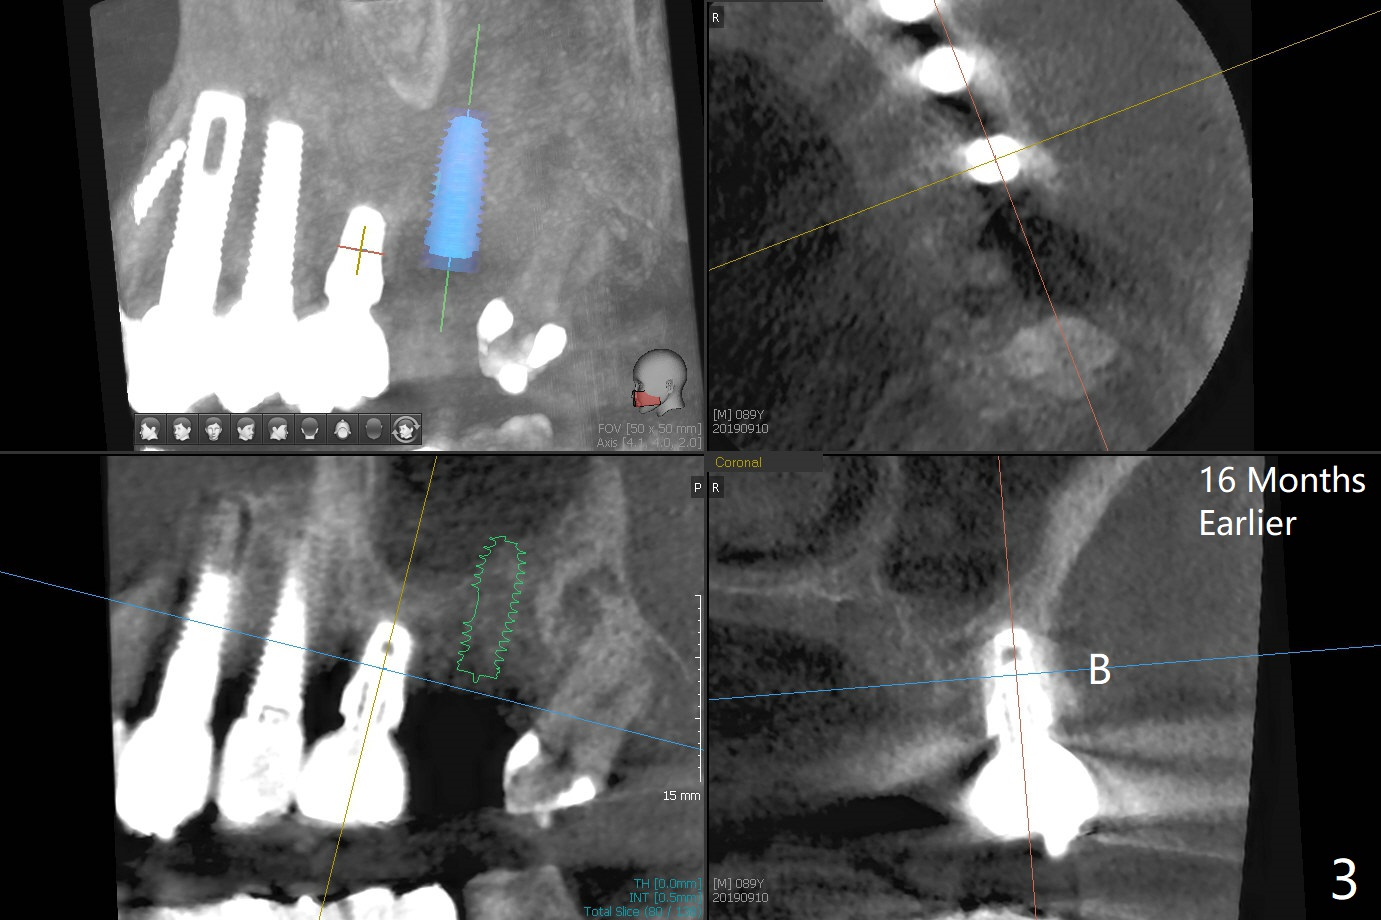

91岁男,刚诊断骨质疏松,准备服用骨质疏松药物Fosamax 70mg 每周一次。主诉左上植牙松动(图一),容易取出,颊侧骨板缺失,上颌窦底板好像完整,清创后,填入皮质骨粉(图二),GEM Cap,牙周胶水,牙周敷料。The buccal plate was present 1 year 4 months earlier (Fig.3). SM implants appear to have rapid bone loss associated with poor bone quality and bruxism.